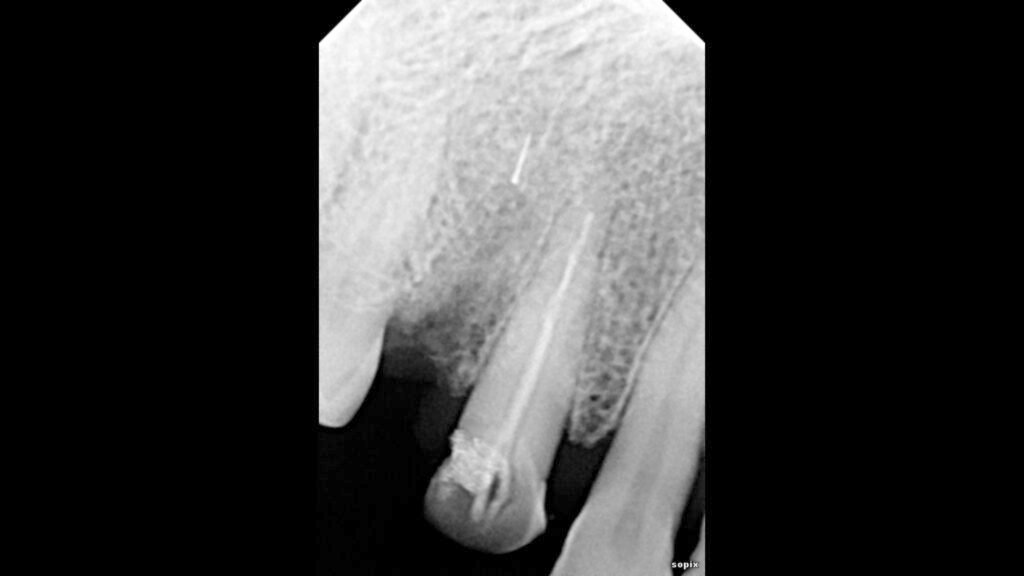

A patient visited our clinic, complaining of pain and occasional swelling on her face after a previous root canal treatment on her right premolar tooth. During our examination and X-rays, I discovered that the earlier dentist had overfilled the canal and, more seriously, had broken a canal shaping file beyond the end of the root, deep into the surrounding bone—showing a lack of proper root canal technique. The X-rays revealed that about 5% of the broken file was still in the canal, while the rest was lodged in the bone.

I then extracted the tooth, which showed overfilled canals, but unfortunately, the broken file did not come out with the tooth. A follow-up X-ray confirmed the file remained in the bone. Using a high-magnification microscope and special illumination, I performed a surgical procedure to carefully remove the broken file from the bone. The patient’s discomfort was resolved after a few days, and she recovered well.